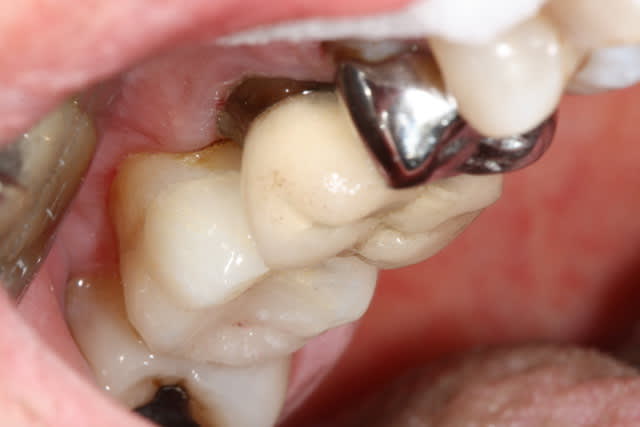

Un petit onlay du dimanche dernier qui m'a fait plaisir. A souligner le travail du prothésiste, content de son boulot après avoir vu les photos.

Pour Sethef: la digue (medium) ne m'a pas gêné, mais le premier clamp que j'ai voulu mettre remontait partiellement sur la limite.

Dent vitale. Il y avait un compo OD et le pan V a lâcher. Limite supra-gingivale.

Ci joint une autre vue.